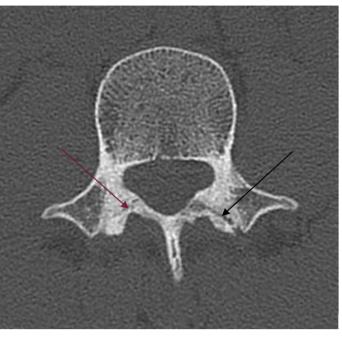

L’image

du jour

Illustration.